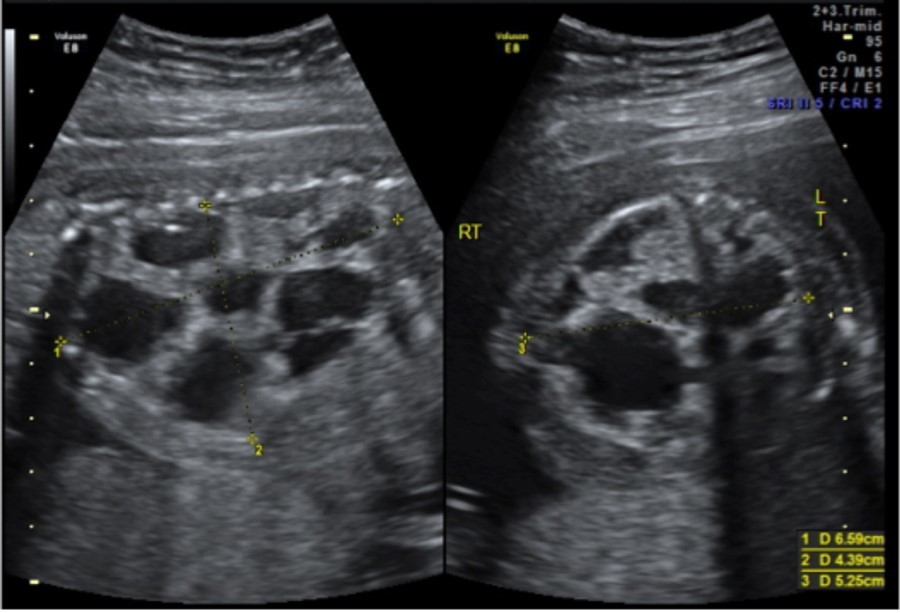

A 33-year-old gravida 1 initially presented for a detailed ultrasound in our office with fulminant fetal hydrops and a noted mass in the left chest. Initial evaluation included maternal viral studies (negative parvovirus, CMV, toxoplasmosis), maternal karyotype (46XX), and amniocentesis (46XX, microduplication in the 16p11.2 region). Given concern for CPAM and hydrops at 20 weeks and 3 days, the patient was referred to a fetal therapy center. Ultrasound at the fetal therapy center showed an estimated fetal weight of 824 grams (>97th percentile) and fetal hydrops (scalp edema of 8mm, skin edema of 4mm, and ascites of 14mm). The diaphragm was intact and the maximal vertical pocket was 6.8 cm. The left chest mass measured 6.6 x 5.3 x 4.4 cm and was multiloculated with microcystic and macrocystic lesions (type 1); the dominant cyst measured 4.0 x 3.2 cm, Figure 1. Secondary to mass effect, the heart was severely displaced into the right chest with a CVR of 3.9cm2. There was no noticeable peristalsis of the cystic structures and no systemic identifiable arterial blood supply. Fetal echocardiogram showed a structurally normal heart significantly shifted in the right chest. After extensive counseling, the patient opted for administration of antenatal corticosteroids and thoraco-amniotic shunt placement. The patient received betamethasone 12mg intramuscularly prior to shunt placement at 21 weeks and 4 days and 21weeks 5 days. Two double pigtail Harrison thoraco-amniotic shunts were placed by inserting a 13 Ga cannular-trocar into the maternal abdomen and uterus (the first shunt into the largest cyst (left, anterior, inferior) and the second into an additional dominant cyst (anterior, central portion of the mass). Both cysts drained completely after insertion. Epidural anesthesia with IV sedation were used as well as tocolytics as needed during the procedure. The post-procedure CVR was 1.3cm2 with decreased mass effect on the heart. Post-operative plan consisted of genetic consultation, fetal MRI, and serial monitoring of the CVR.

Figure 1.CPAM noted at initial fetal surgery consultation; sagittal view on the left and transverse view on the right